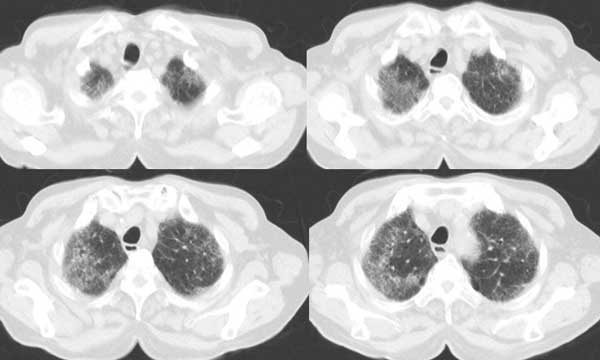

以下是引用同在2006-7-20 21:01:00的发言:[br]间质性肺炎,两肺纤维化,肺气肿。

以下是引用dalianren在2006-7-20 21:23:00的发言:[br]我考虑是肺泡蛋白沉积症:典型表现为两肺内散在片状\"磨玻璃\"样混浊区呈地图样分布.

以下是引用lj0804在2006-7-21 12:57:00的发言:[br]支持[br]我考虑是肺泡蛋白沉积症:典型表现为两肺内散在片状\"磨玻璃\"样混浊去呈地图样分布.